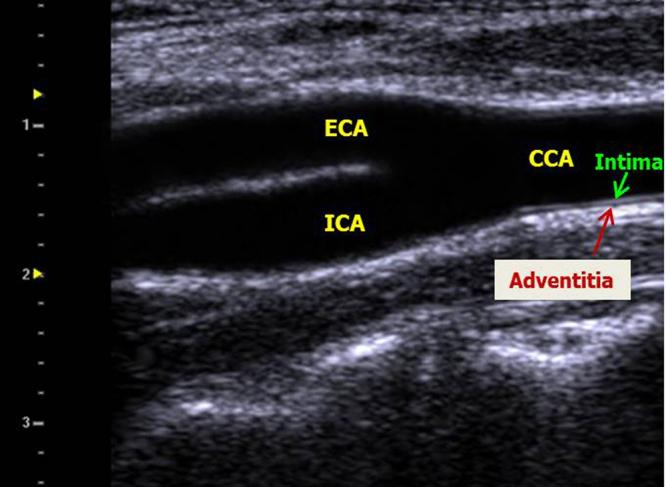

In this multi-centric study, 1229 subjects with age ≥30 years and no previous cardiovascular disease (CVD) underwent CVD risk factor assessment and CIMT measurement. Mean far wall common carotid artery IMT was measured on both sides and averaged.

方法

在这项多中心研究中,1229名年龄≥30岁且既往无心血管疾病(CVD)的受试者接受了CVD危险因素评估和CIMT测量。测量双侧颈总动脉远壁的平均IMT并取平均值。